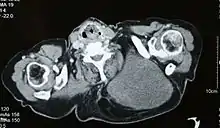

ساركومةٌ شَحْمِيَّةٌ[1] أو غرن شحمي[1] (بالإنجليزية: Liposarcoma) هي سرطان ينشأ من الخلايا الدهنية الموجودة في الأنسجة الرخوة العميقة مثل تلك الموجودة في الفخذ والتجويف خلف الصفاق.[2] الساركومة الشحمية هي من السرطانات النادرة والتي تشبه إلى حد كبير الخلايا الدهنية أثناء فحصها تحت المجهر.[3] تكون في الغالب سرطانات كبيرة وتميل لإرسال خلايا ساتلة صغيرة والتي تمتد خارج حدود الورم.

التشخيص

يتم تشخيص المرض بعد الفحص المجهري للأنسجة من خلال الخزعة أو الاستئصال. في الغالب توجد أرومة الشحمية "lipolaste" وهي عبارة عن خلايا تحتوي على سيتوبلازم ذو فجوات مفرطة العدد ونواة لامتمركزة منبعجة بسبب الفجوات.